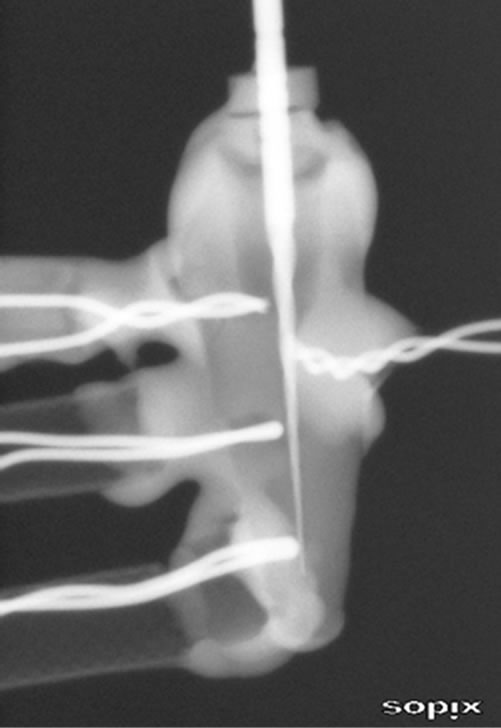

T type (copper-constantan) thermocouples were made by twisting together one end of each of two wires (0.1 mm). The joint was silver soldered to prevent the wires from unwinding under the influence of cavitation and to enhance electrical contact between the two wires. Spaghetti-type plastic insulation was placed over each wire to within 3 mm of the solder joint. This 3 mm section of wire was coated with a flowable compomer restorative material (Dyrect flow, Dentsply) to keep the wires separated and to facilitate handling. Four thermocouples were attached to the tooth: one was attached to the root surface and three were inserted into the root canal at 3, 9, and 15 mm from the apical foramen, respectively (Figure 1). The free ends of the wires were attached to a data recorder (LogoScreen 500 cf; Jumo, Fulda, Germany) running PCA 3000 software (Jumo, Fulda, Germany). The accuracy of the temperature measurements was verified to be 0.1˚C in a pilot study, in which results from a thermocouple submerged in water at room temperature were compared with calibrated thermometer readings.

Figure 1. Each test specimen was constructed by placing three thermocouples inside the root canal; in addition, one thermocouple was attached to the surface of the root canal.